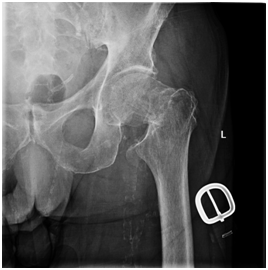

An 81-year-old man presented to the emergency department with a history of a fall while trying to pivot on his prosthesis. He complained of left hip pain, radiating into his groin. Pain was also elicited with log roll. He had a history of a left below-knee amputation following a history of peripheral vascular disease with a failed bypass procedure. Radiographic evaluation revealed a displaced basicervical femoral neck fracture of his left lower extremity (Figure 1).

Figure 1 AP view of left hip displaying a displaced basicervical fracture.